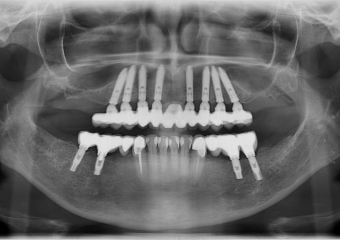

Raio X com implantes Cone Morse superiores e próteses provisórias